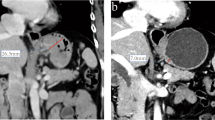

The CT images in arterial and venous phases were isotropically resampled by using trilinear interpolation in Artificial Intelligence Kit software (A. K, version: 3.3.0. R, GE Healthcare, USA) with a voxel size of 1 × 1 × 1 mm to minimize the effect of different scanning protocols or equipment on the radiomics features [29]. Region of interest (ROI) segmentation was performed by delineating around the tumor outline for the largest cross-sectional area in the CT axial plane (Fig. 1). Care was taken to avoid the gastric cavity and stomach contents, fatty tissue around the stomach wall and blood vessels when segmenting. Each ROI was outlined by a radiologist (L.C. 6 years of experience in abdominal imaging diagnosis) and supervised by a radiologist (Z.H., 8 years of experience in abdominal imaging diagnosis). To ensure the reliability and reproducibility of the radiomics features, 30 patients were randomly selected for their data to be segmented. For an analysis of interobserver agreement, a radiologist (L. CC) conducted the first-time whole-dataset segmentation, and another radiologist (H.W., 7 years of experience in abdominal imaging diagnosis) who was supervised by a radiologist (L.L., 9 years of experience in abdominal imaging diagnosis) delineated the images of the 30 selected patients during the same period. For analysis of intraobserver agreement, the radiologist (L. CC) repeatedly conducted segmentation 1 month after the first delineation.

Hypofractionated adenocarcinoma of the esophagogastric junction (AEG) in a 63-year-old man. A CT venous phase axial image before neoadjuvant chemotherapy (NAC), Borrmann staging type I, thickest tumor diameter of 3.4 cm. B Schematic diagram of region of interest (ROI) segmentation on ITK-SNAP software. C CT venous phase axial image after NAC, lesion near disappearance, and insignificant gastric wall thickening. D Postoperative pathological images; fibrous tissue hyperplasia with chronic inflammatory cell infiltration was seen; no tumor cells remained; and tumor regression was obvious (HE × 200). Hypofractionated AEG in a 36 years old man. E CT venous phase axial image before neoadjuvant chemotherapy (NAC), Borrmann staging type III, thickest tumor diameter of 3.2 cm. F Schematic diagram of region of interest (ROI) segmentation on ITK-SNAP software. G CT venous phase axial image after NAC, significantly smaller lesions with reduced enhancement. H Postoperative pathological images showed more chronic inflammatory cell infiltration in the mucosal and lamina propria layers with focal fibrosis (HE × 200)